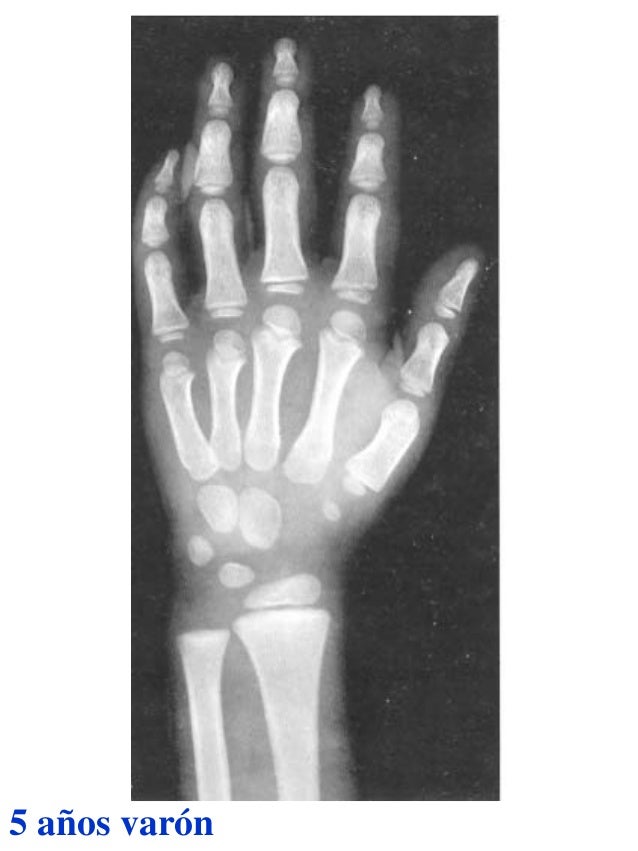

Figura 2 Imágenes de radiografías de mano y muñeca izquierda del

Figura 2 Imágenes de radiografías de mano y muñeca izquierda del Tablas De Greulich Y Pyle Edad Osea The greulich and pyle atlas is used to estimate the age of children and adolescents. El método de greulich y pyle(1) es un método simple de valoración de la edad ósea en pacientes pediátricos. El diagnóstico y la clasificación se basan en el examen físico, el análisis del crecimiento, la maduración ósea, la ecografía de útero y gónadas, y los. Tablas De Greulich Y Pyle Edad Osea.